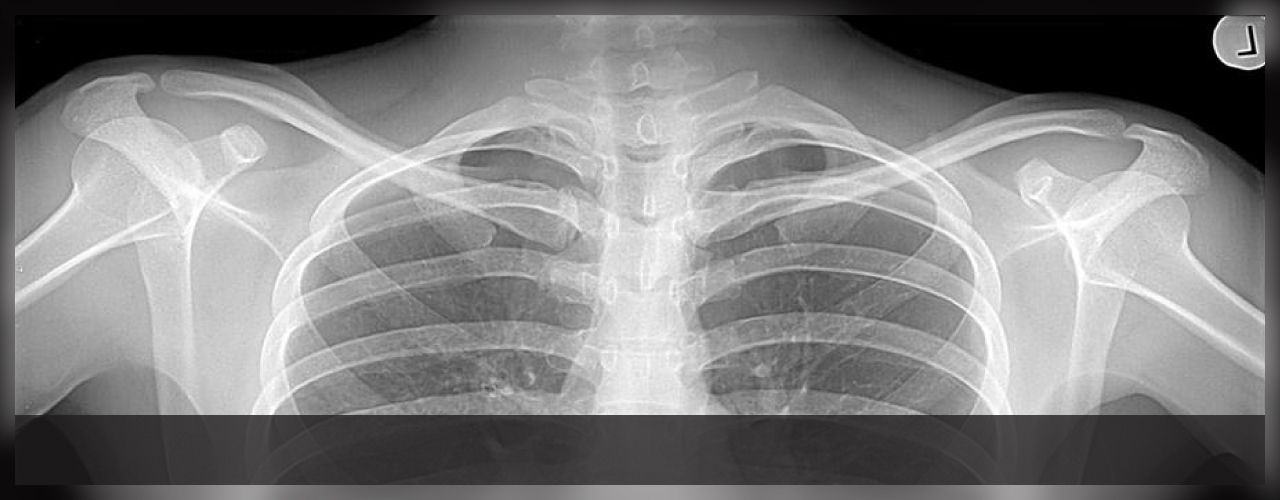

Molto spesso, una volta riconosciuto il difetto di fabbricazione del dispositivo, l’unica soluzione risulta essere la rimozione e sostituzione dello stesso con un apparecchio similare. Questa necessità costringe il paziente ad essere sottoposto ad uno o più interventi chirurgici con lo scopo di eliminare il prodotto difettoso sostituendolo con uno migliore.